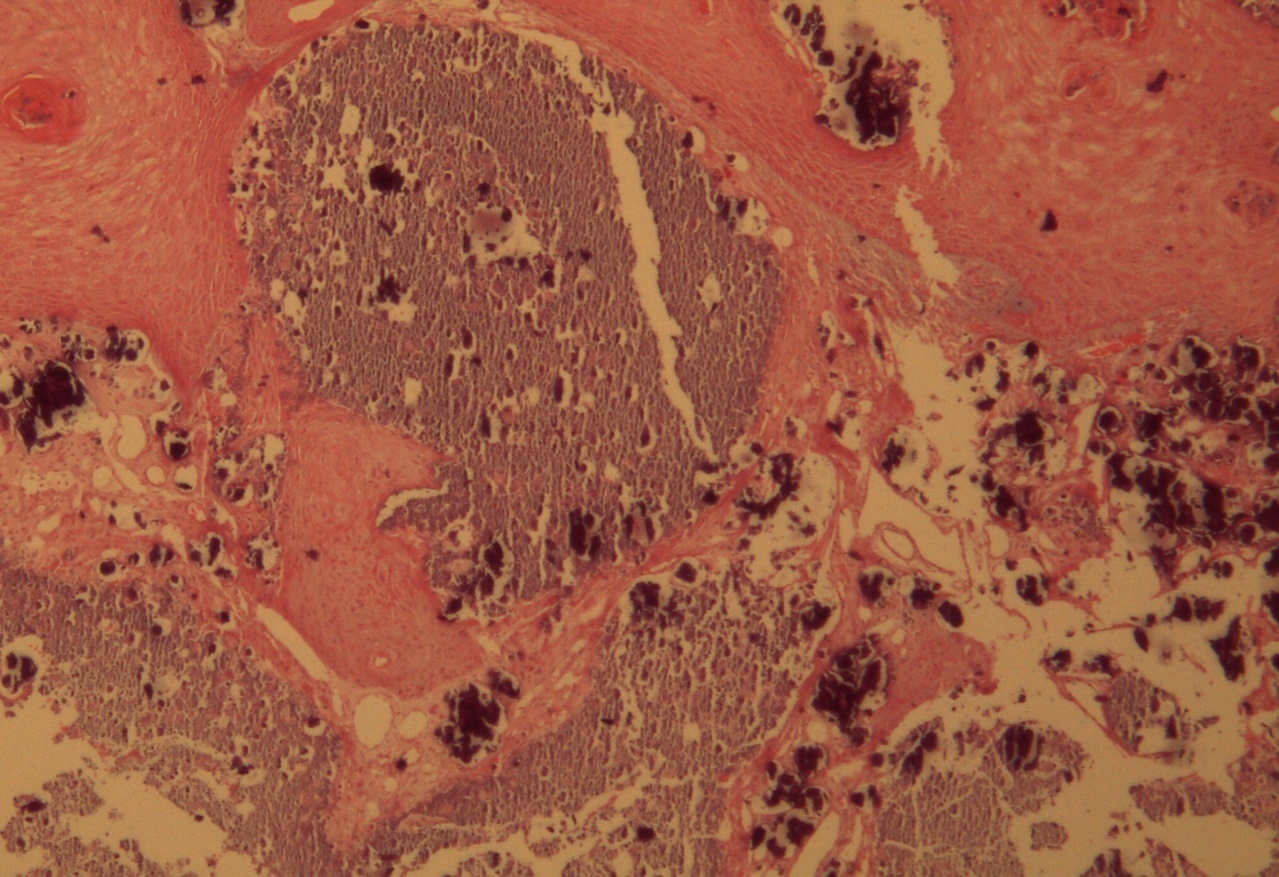

A 9-year-old male patient who was treated in the dermatology service for a progressively growing keratotic nummular dermal lesion on the right knee. With the clinical judgment of viral wart, the lesion was removed. In the Pathology Service, a nummular keratotic lesion of 0.5 cm in maximum dimensions was received, which crackled when cut. Figure 1, Figure 2, Figure 3, Figure 4, Figure 5

Figure 4.Presence of calcium deposits in the dermal vessels. Detail. HE 400x.

Presence of calcium deposits in the dermal vessels. Detail. HE 400x.